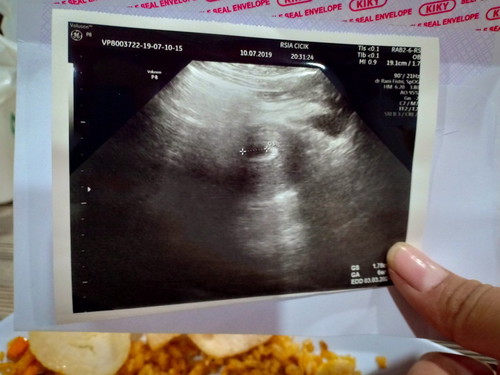

uk 6week janin belum kelihatan

Bun ini foto usg saya uk 6week tapi belum kelihatan janin nya kata dokter? Disuruh dateng 2week lagi buat mastiin janin nya berkembang atau gak? Normal gak bun? Ada yang kayak saya gak bun?